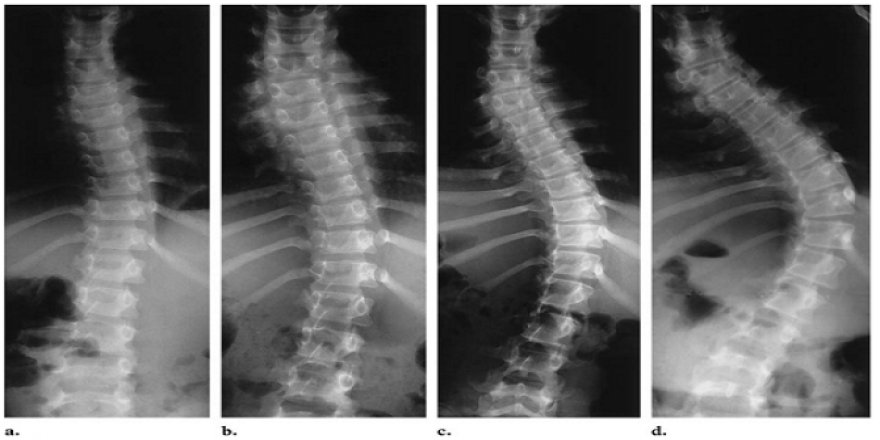

Hareketsizlik omurga sağlığını bozuyor

Kız çocuklarında skolyoz daha fazla görülüyor